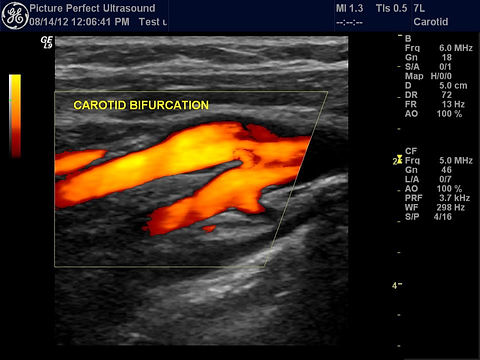

경동맥 초음파는 목 양쪽의 경동맥(carotid artery)에 초음파 탐촉자를 대고 혈관 벽 두께(IMT), 혈류 속도, 협착(좁아짐) 여부를 실시간으로 관찰하는 비침습적 영상 검사입니다.

- 초음파의 색도플러·파워도플러 모드로 플라크 혈류와 내포된 출혈 여부를 평가할 수 있습니다.

- 즉시 결과 상담 – 촬영 영상을 보며 의사가 협착률·IMT·혈류 속도(Vmax, PSV, EDV)를 설명합니다.